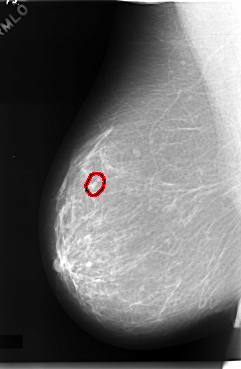

C_0057_1.RIGHT_MLO

RIGHT_CC LINES 5944 PIXELS_PER_LINE 3880 BITS_PER_PIXEL 12 RESOLUTION 50 OVERLAY

RIGHT_MLO LINES 5904 PIXELS_PER_LINE 3856 BITS_PER_PIXEL 12 RESOLUTION 50 OVERLAY

FILE: C_0057_1.RIGHT_MLO.OVERLAY

TOTAL_ABNORMALITIES 1

ABNORMALITY 1

LESION_TYPE CALCIFICATION TYPE PLEOMORPHIC DISTRIBUTION CLUSTERED

ASSESSMENT 4

SUBTLETY 3

PATHOLOGY MALIGNANT

TOTAL_OUTLINES 1

BOUNDARY